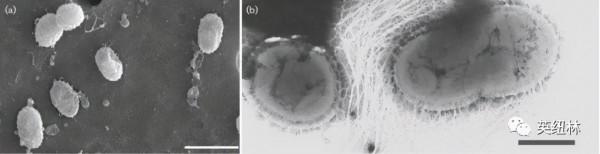

Akk 是一種橢圓形的革蘭陰性菌,是人體腸道的常駐民,占人體微生物群落的3-5%。它能在腸道粘液層中生長,並利用宿主分泌的粘蛋白“為食”,從而透過競爭性排斥的方式在腸道內定居並保護腸道免受病原體的侵害。雖然 Akk 菌以粘蛋白作為能量來源,但大量觀察證實,Akk對腸道粘液層厚度和腸屏障完整性存在正向調節作用。